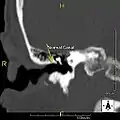

Normal ear canal

The normal ear canal is approximately 7 mm in diameter and has a volume of approximately 0.8 ml (approximately one-sixth of a teaspoon).[4] As the condition progresses, the diameter narrows and can even close completely if untreated, although sufferers generally seek help once the passage has constricted to 0.5-2 mm due to the noticeable hearing impairment. While not necessarily harmful in and of itself, constriction of the ear canal from these growths can trap debris, leading to painful and difficult to treat infections.